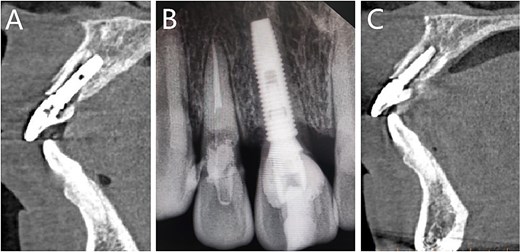

Postoperative CT scans revealed an intact buccal root segment, with a 1 mm distance between the implant and the segment (Fig. 4A). X-ray, performed one month later, showed that the implant was located in the middle of the edentulous area, while bone height was comparatively at the same level as the neck of the adjacent tooth in mesial and distal (Fig. 4B). CBCT, performed 6 months later, showed that the interval between the root segment and implant was filled with new bone tissue (Fig. 4C). The gingiva was in good condition, meanwhile, the soft tissue of the buccal side proliferated toward the incisal edge (Fig. 5A). Impression was performed with personalized mold tool to obtain individual emergence profile (Fig. 5B–D). Eventually, a porcelain crown was placed on the custom abutment.

Follow-up imaging examinations. (A) Postoperative CT; (B) X-ray performed one month later; (C) CBCT performed 6 months later.